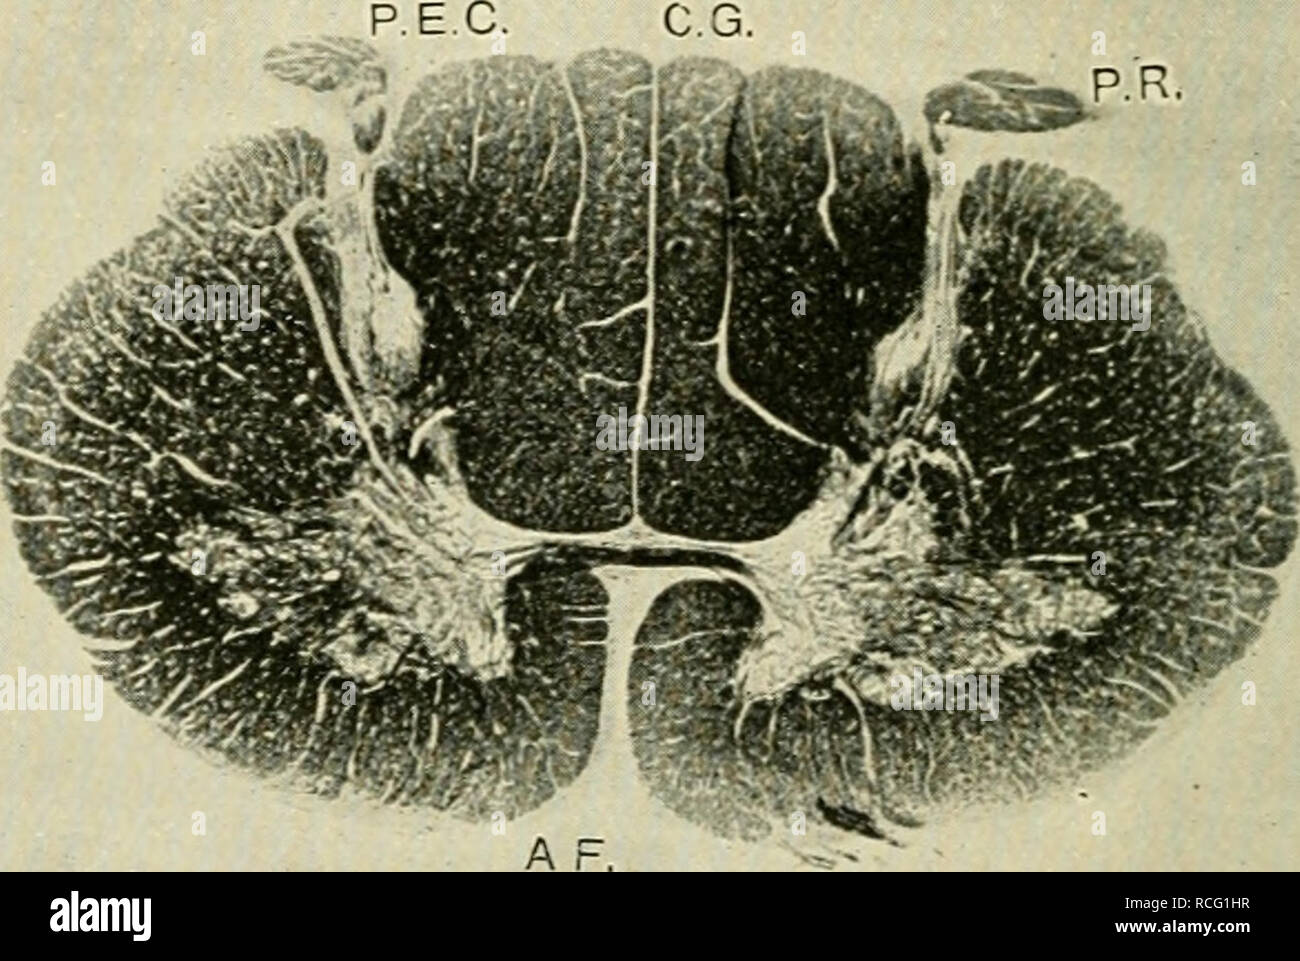

Éléments d'histologie. L'histologie. ^7 éléments d'Histologie. La dure-mère, ainsi que l'arachnoïde, envoie des prolongements sur les racines nerveuses à ; et le sous-dural et sous-espaces sont arachnoidal a continué dans les